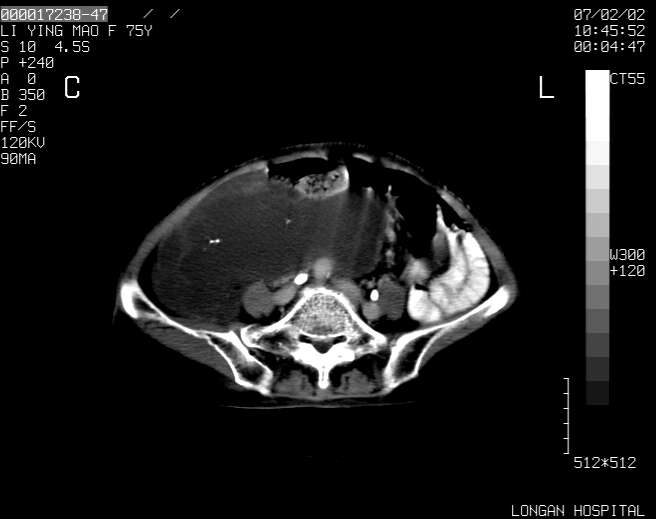

以下是引用dyqct在2007-2-10 8:53:00的发言:[br]考虑:1、肝脏多发囊肿[br] 2、左肾囊肿,右肾多发结石并积水。[br] 3、右胸少量积液。[br] 4、右肾周包裹性积液或淋巴管瘤(有见缝就钻的征象、薄隔、小结节状钙化)?[br] 5、腰椎动脉瘤样骨囊肿?[br] [br] [br]